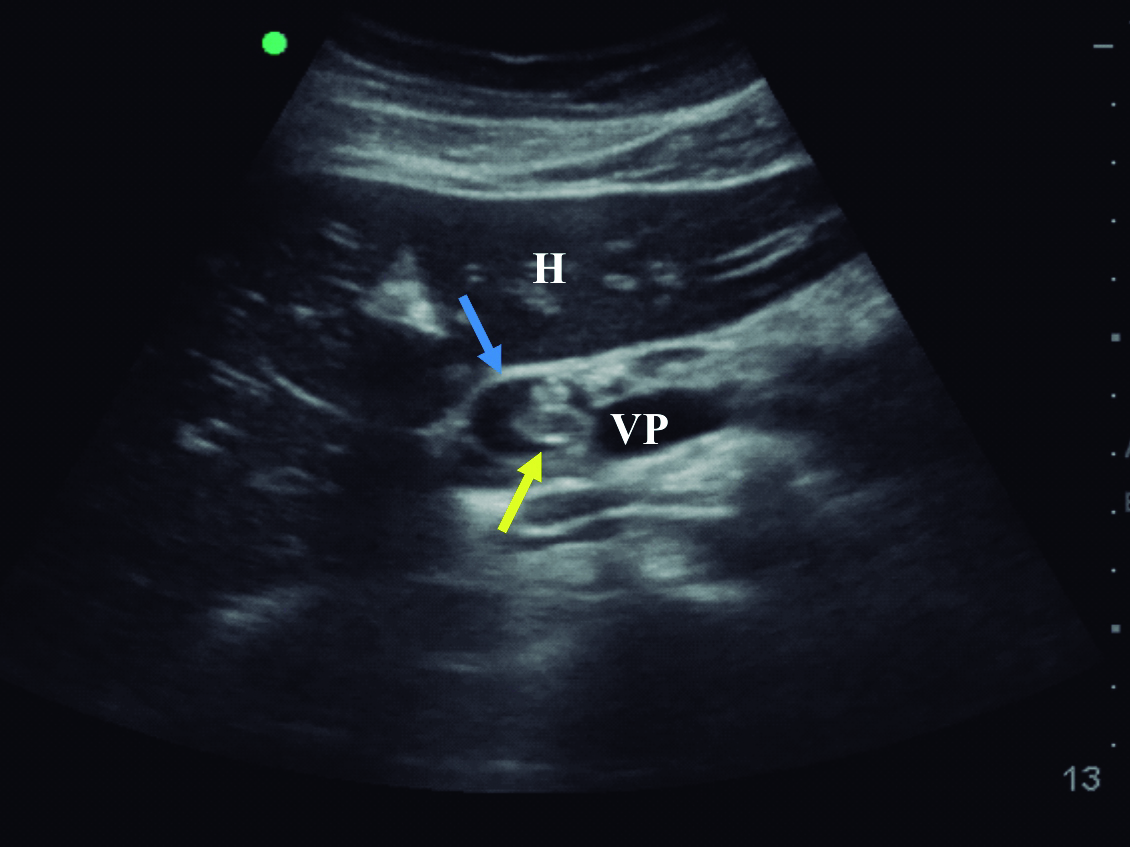

El ultrasonido de abdomen realizado al ingreso mostró vía biliar principal dilatada, a predominio del conducto hepático izquierdo en cuyo interior se observó imagen trilaminar, alargada, sin sombra acústica posterior, compatible con parásito. El extremo cefálico del parásito alcanza el origen de los canalículos de los segmentos póstero-laterales izquierdo y su extremo caudal se extiende dentro de la luz del conducto hepático común y el colédoco. El diámetro mayor del colédoco alcanzó 12mm, el parásito se detectó alcanzando la zona de la papila duodenal, estando plegado sobre sí mismo dentro de la vía biliar principal (Fig. 1).

Figura 1. Ultrasonido en modo B

a) Corte transversal a nivel de epigastrio, en el cual se identifica colédoco dilatado (flecha azul), ocupado por el Ascaris plegado sobre sí mismo (flecha amarilla).

b) Corte longitudinal sobre el colédoco supraduodenal, en el cual se observa el

Ascaris plegado sobre sí mismo (flechas amarillas) dentro del colédoco dilatado

(flecha azul). H: Lóbulo hepático izquierdo, E: Corte transversal del antro gástrico,

VP: Vena porta.

En el ultrasonido, la apariencia de los helmintos depende de la sonda empleada. Con transductores convexos de baja frecuencia se visualizan típicamente en un corte longitudinal como una imagen trilaminar y sin sombra acústica, las líneas ecogénicas externas corresponden a las paredes del parásito y la imagen lineal ecogénica en su interior corresponde al tracto digestivo del mismo. Si se visualizan transversalmente en un conducto biliar dilatado, aparecen como una imagen tubular, en diana con bordes ecogénicos y centro anecogénico. Con una sonda lineal de alta frecuencia (mayor a 7.5MHz) los helmintos se observan en corte longitudinal como una imagen de 4 líneas, representando las dos exteriores la interfaz entre el parásito y lo que lo rodea y las dos interiores el intestino de la lombriz. (5, 7, 13) Estas imágenes características fueron las que llevaron al diagnóstico en la paciente que se presenta en este caso. Algunas veces puede observarse la movilidad de los helmintos vivos, pueden estar enrollados y si son múltiples, pueden llenar completamente el conducto biliar y producir el “signo de espagueti”. Si están muy compactados en los conductos biliares, pueden aparecer amorfos y manifestarse como pseudotumores hiperecogénicos. (6) Debe realizarse exploración de la vía biliar principal y accesoria ya que en ocasiones se ubican dentro de la vesícula biliar. También debe valorarse el conducto pancreático para descartar Ascaris en esta localización. El empleo de la sonda lineal en ocasiones es de utilidad para mejorar la resolución espacial y de ese modo caracterizar mejor los parásitos. (1)